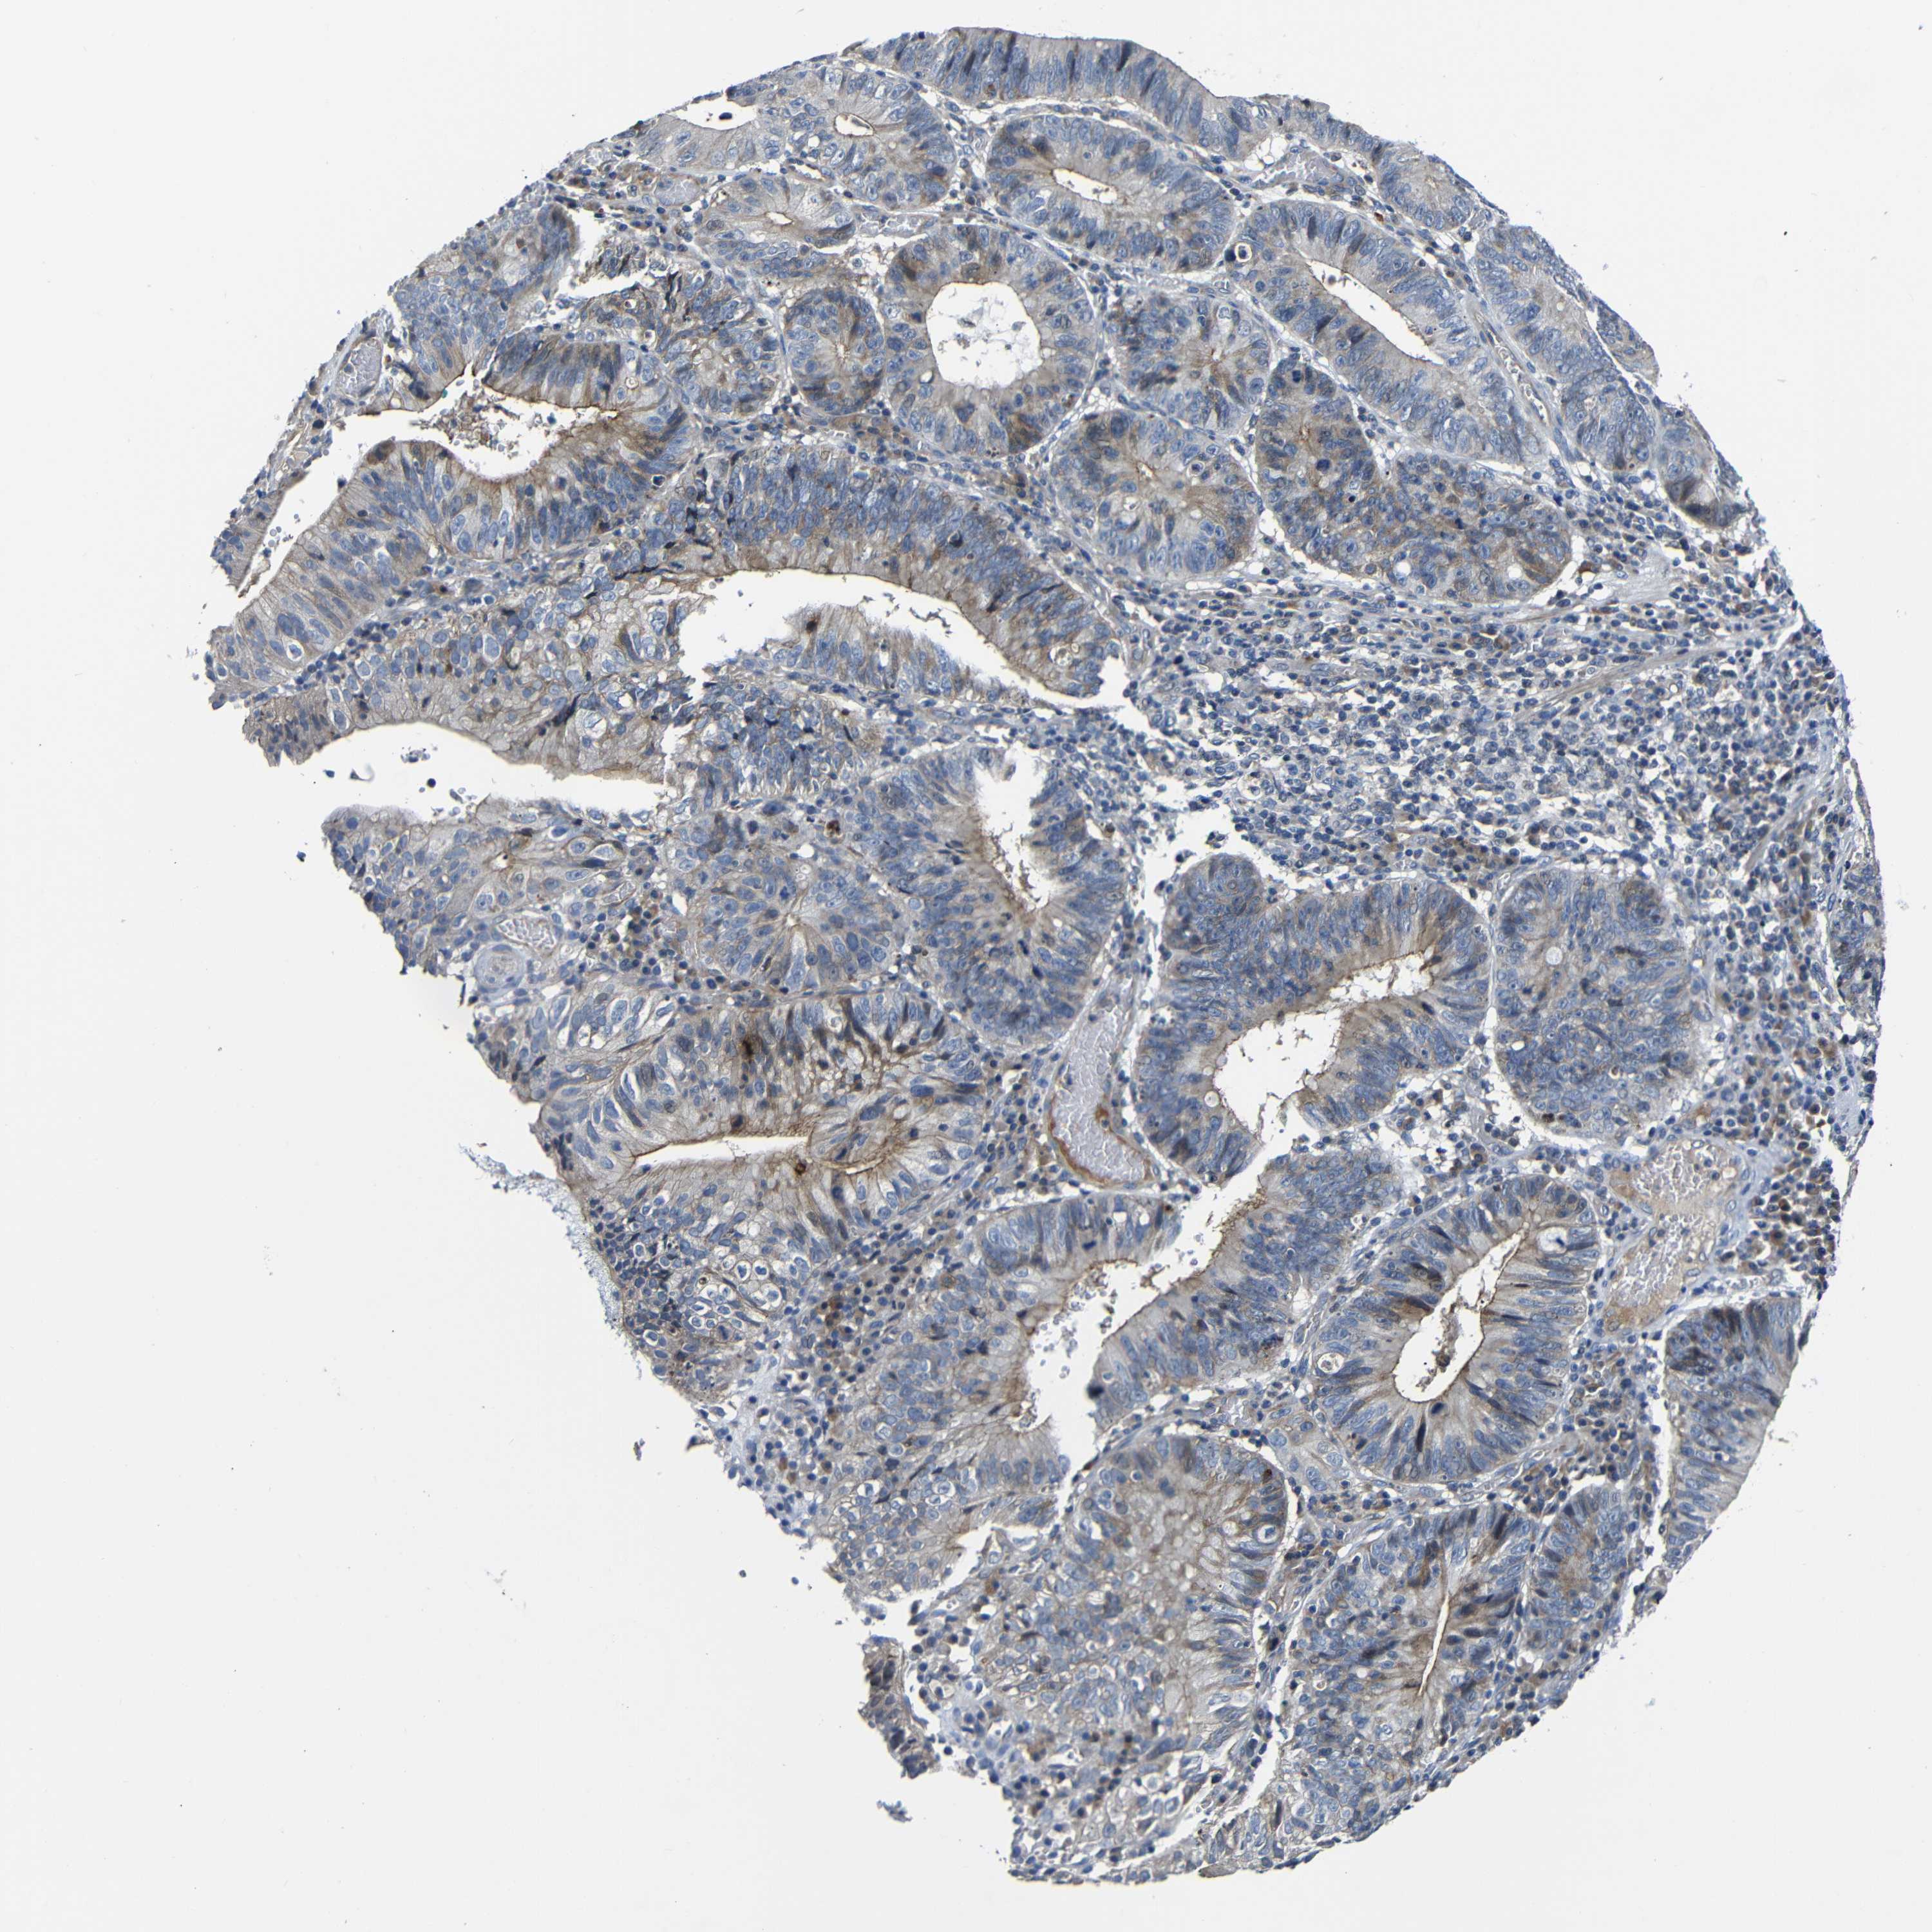

STOMACH CANCER - Protein expressioni

A mouse-over function shows sample information and annotation data. Click on an image to view it in a full screen mode. Samples can be filtered based on level of antibody staining by selecting one or several of the following categories: high, medium, low and not detected. The assay and annotation is described here.

Note that samples used for immunohistochemistry by the Human Protein Atlas do not correspond to samples in the TCGA dataset.

Antibody stainingi

Antibody staining in the annotated cell types in the current human tissue is reported as not detected, low, medium, or high, based on conventional immunohistochemistry profiling in selected tissues. This score is based on the combination of the staining intensity and fraction of stained cells.

Each image is clickable and will lead to virtual microscopy that enables deeper exploration of all samples and also displays staining intensity scores, fraction scores and subcellular localization as well as patient and tissue information for each sample.

HPA030212

HPA030213

HPA030214

HPA030215

CAB013496

Adenocarcinoma, NOS